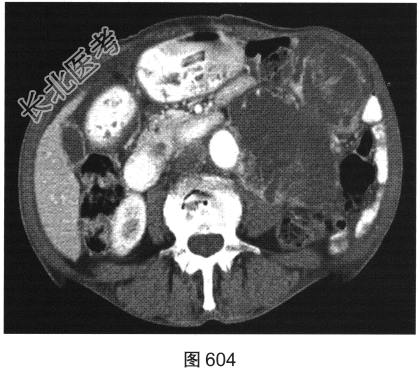

- [材料题] 患者女性,85岁,腹主动脉瘤破裂手术修复后,腹部疼痛。患者行腹部CT检查,见图603~图607。

- 简答题1、请对该病变CT影像表现进行描述。